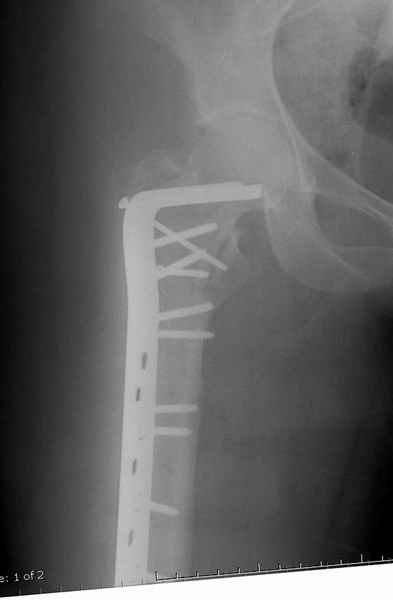

Уважаемые коллеги.Ко мне обратился мой коллега, весьма опытный травматолог, владеющий практически всеми видами остеосинтеза, с просьбой собрать мнения по поводу нескольких клинических случаев - два перелома бедра и перелом плеча.Если можно, подтвердите свое мнение иллюстрациями аналогичных ситуаций, либо ссылками - для клинического разбора. Бедро 1:Женщина 1929 г.р. Травма в результате падения 14.09.04г.Диагноз Закрытый оскольчатый чрезвертельный перелом правой бедренной кости со смещением отломков.Сопутствующие заболевания: ИБС, стенокардия напряжения, постинфарктный кардиосклероз (ИМ в 1992 году); гипертоническая болезнь 2 ст.; ожирение 3. Дополнительные данные - сохранная старушка.Спасибо.С уважением Александр Артемьев

Это 4-фрагментный перелом, традиционно-современная фиксация - это динамический бедренный винт, DHS. Либо какой-либо из проксимальных бедренных гвоздей, предназначенных для ранней полной нагрузки, из-за меньшего доступа, других преимуществ перед DHS нет. Если доступен только реконструкционный гвоздь, то винты вводить надо очень точно и аккуратно субхондрально, т.е. максимальной длины, а то прорежутся в головке.

Вот пример наших американских коллег про DHS. Видно, как стелескопировались отломки, хотя поначалу был оставлен диастаз.

Типичный остеопорозный вертельный перелом , не стабильный, 4-х фрагментный, базоцервикальный. Лечение оперативное не позднее 48 часов после перелома, чем раньше тем лучше, если общее состояние позволяет.

Фиксатор или DHS 130 градусов или PFN с короткой ножкой. Если DHS, то шуруп должен находиться в центре шейки и дополнительно еще простой длинный шуруп против ротации в проксимальной части шейки над шурупом DHS. Полную нагрузку на ногу начать через 6 недель.

У нас скорее бы всего использовали Г-образную пластину. Если есть возможность - DHS.

В такой ситуации я бы установил Gamma Nail короткий Мне кажется что это самый простой и быстрый способ решить эту проблему

Совершенно согласен с Mike, если у вас на очереди все представители компаний, предлагающие свои услуги, все методы хороши: пластины и шурупы, Compression Hip screw, Blade Plate, DCS, Intramedullary Nails:

Большие преимущества у интрамедуллярных штифтов, метод хорош и можно произвести из минимального доступа, но во время операции необходимо контролирование варуса, затем приступить к блокированию.

Для молодых больных выбрал бы тактику fixed angled device 95 degree Blade Plate, техника непрямого метода репозиции, который описал в своей книге Jeff Mast, Planning and Reduction Technique in Fracture Surgery ( method of Inderect Reduction), репозиция и фиксация происходит за счет фиксации головки бедра к femoral shaft с помощью пластины, а что в середине должны репонироваться без больших усилии и без разрушения мягкотканого соединения c медиальной стороны.